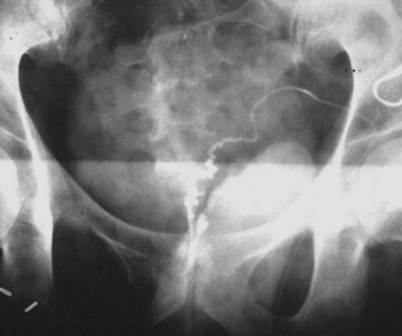

If a large amount of fluid is found in the vasal lumen and microscopic examination reveals the presence of sperm, the obstruction is toward the seminal vesicle end of the vas. In these cases the vas is usually markedly dilated. A 2-0 Proline suture can be passed toward the seminal vesicle end of the vas and a clamp placed on the Proline when the suture passes no farther. This is particularly useful for delineating the site of inguinal obstruction from prior groin surgery. If the obstruction is proximal to the inguinal scar, formal vasography is performed by passing a No. 3 whistle-tip ureteral catheter toward the seminal vesicle end of the vas. A 16-Fr Foley catheter is placed in the bladder, and the balloon is filled with 5 mL of air. Placing the balloon on gentle traction before vasography prevents reflux of contrast into the bladder, which can obscure detail (Fig. 22–5). The air-filled balloon also identifies the location of the bladder neck relative to any obstruction. After the vasa have been cannulated, vasograms are performed with the injection of 0.5 mL of water-soluble contrast media (Fig. 22–6). If vasography reveals obstruction at the site of the ejaculatory ducts (Fig. 22–7), indigo carmine is injected in both vasa to assist a transurethral resection (TUR) of the ejaculatory ducts (see Diagnosis later). If both vasa are visualized after injection of contrast into only one vas (Fig. 22–8), it means both vasa empty into a single cavity, usually a midline ejaculatory duct cyst.

Figure 22–5 Placing the balloon on gentle traction before vasography prevents reflux of contrast into the bladder, which can obscure detail.

Figure 22–8 Both vasa are visualized after injection of contrast into one vas only, revealing distal obstruction.